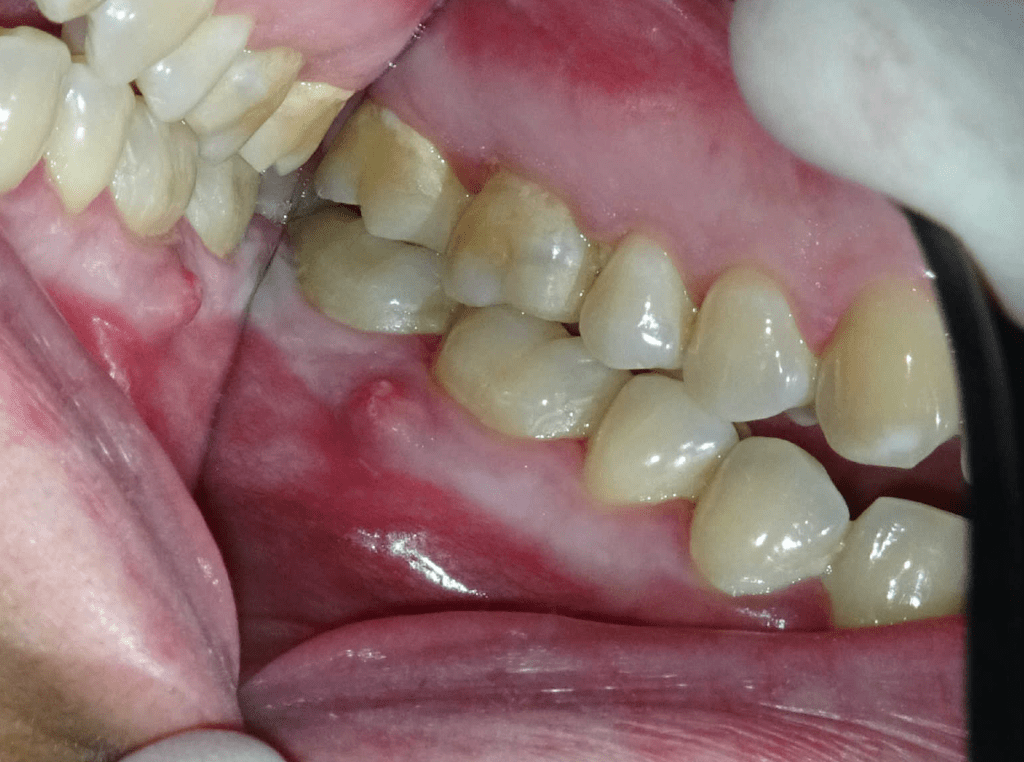

Endodoncias a traves de coronas

20 molar superior a traves de corona